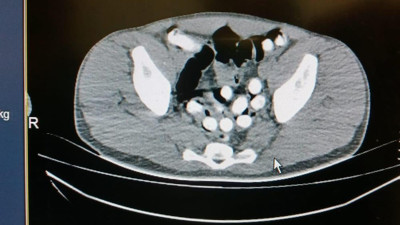

Ne bulduysa mideye indirmiş. Mide değil sanki hurdalık Van'da karın ağrısı şikâyetiyle hastaneye başvuran 35 yaşındaki gencin midesinden 1 liralık 83 madeni para, pil, mıknatıs, çivi, cam parçaları, taş ve vida gibi 233 cisim çıkarıldı.